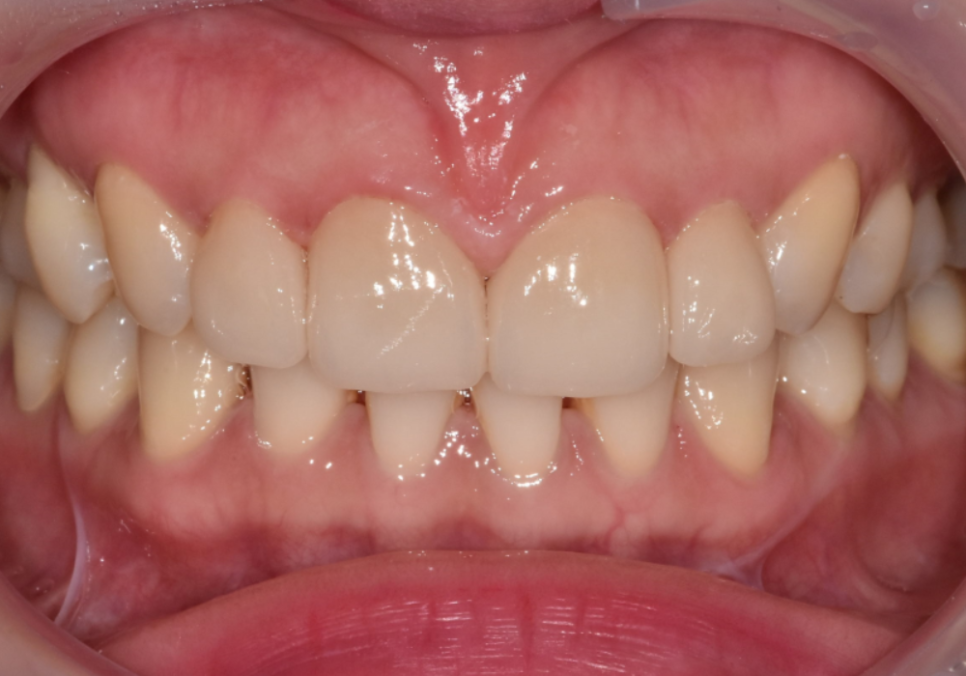

이런 경우에는

앞니 전체를 건드리지 않아도

241102

문제가 되는 치아 한 개만

라미네이트로 개선해도

인상에 충분한 변화를 줄 수 있습니다.

241102(전) 241116(후)

실제로 이 환자분도

한 개만 치료했지만,

웃을 때의 인상은

여러 개를 바꾼 것처럼

훨씬 안정적으로 보이게 되었습니다.